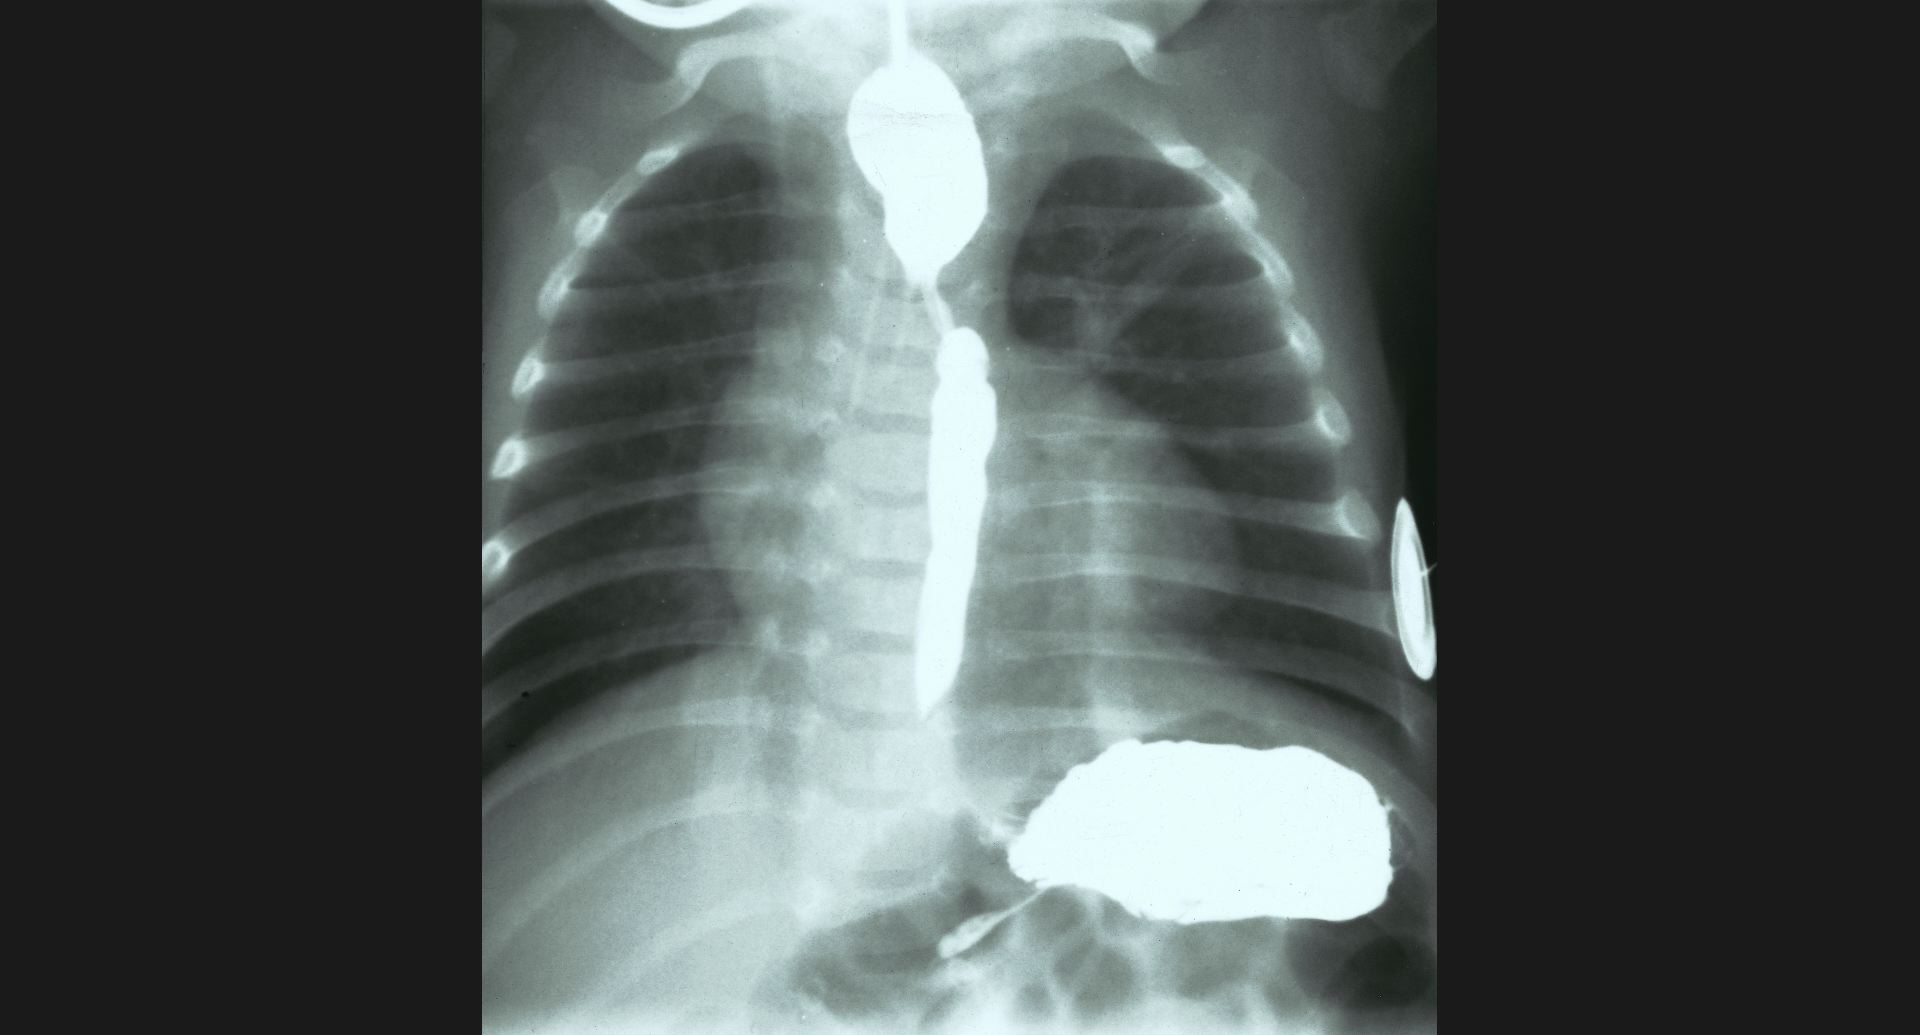

fig.3(105KB)

:食道狭窄、肺炎食道狭窄は、double aortic archによる。

肺炎は、造影の細かいところ。